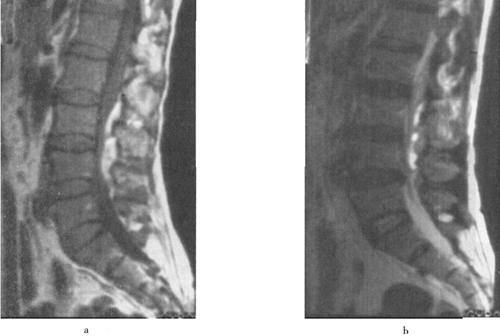

(2)出血:包括脊髓内出血和硬膜外血肿(图7-14至图7-16)、硬膜下出血和蛛网膜下腔出血等。脊髓内出血是不可逆损伤,其信号改变随时间变化较大。急性期(24h内)髓内出血灶在T1WI呈中等信号或不均匀信号,在T2WI呈中央低信号出血灶,外围水肿为高信号。亚急性期(3~5d)血肿在T1WI信号逐渐升高,在T2WI信号仍较低,慢性期血肿在T1WI和T2WI均为高信号。脊髓硬膜外血肿、硬膜下出血和蛛网膜下腔出血,在MRI上表现为椎管内脊髓外的软组织增厚影,在T1WI呈不均匀低信号,在T2WI为高信号。硬膜外出血脊髓受压移位明显。

图7-14 腰椎后柱骨折伴硬膜外出血,马尾受压。T1W(a)和T2W(b)矢状成像,椎管后方硬膜外可见T1W和T2W均为高信号的血肿

图7-15 颈髓挫裂伤:T1W(a)T2W(b)矢状面,脊髓增粒为髓水肿所致,T1W和T2W信号增高。横断面(c)脊髓内可见斑片状出血灶,硬膜外血肿T2W亦呈高信号,脊髓压迫向右后移位。颈后方软组织出血水肿,在T2W亦为高信号

图7-16 L1压缩骨折,脊髓挫裂伤:T1W(a)和T2W(b)矢状面,L1椎体呈楔状变形,椎体骨折,但无移位。后方硬膜外及脊髓内可见高信号血肿,在横断位T1W(c)、T2W(d)成像,如箭头所示脊髓圆锥内椭圆型高信号影,为出血所致。椎体骨髓水肿及出血。

(3)脊髓挫伤:脊髓挫伤是脊髓水肿伴局灶性出血,在T1WI小的出血灶可呈高信号,邻近水肿为等低信号,T2WI呈混杂高信号(图7-16)。